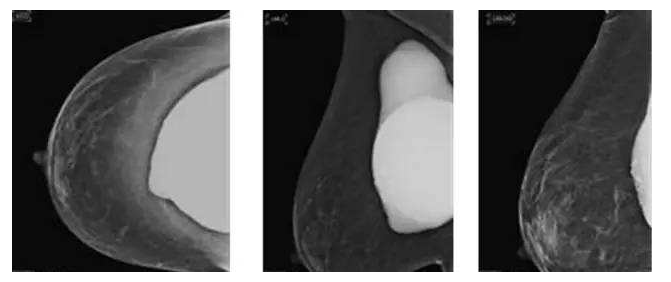

假体隆胸10年后将面临什么样的问题?

假体隆胸手术发展至今已有几十年历程,随之时代的发展,医学的进步,现代隆胸技术在不断升级,假体质量也在不断提高。现代信息的广泛传播,也让受众对于隆胸手术的了解全面化。一台成功的隆胸手术可以维持10年的时间,那么为什么是10年成为了隆胸的关键时期?10年后隆胸的人会面临怎样的问题?

假体隆胸没有终身性的理论,并不代表它就真的不能终身,只是出于健康考虑,我们需要在10后将假体可能存在的、不可预见的问题更加以关注。所以无论是专家、还是假体厂商对于假体的寿命都无法给予准确的答案。

置入假体在一定时间内可能出现老化现象,所以专家建议平均8-12年更换一次假体为宜,进口的硅胶假体维持时间会更长到10-20年,甚至更久。

因为假体质量不同、医生操作方式不同、个人体质存在差异,所以具体的存放时间无法被预估。所以假体隆胸10年后,应每年进行B超、核磁共振检查,以确保假体的完整性和安全性,排除并发症,如遇问题,可尽早进行处理。

假体老化最常出现的现象,比如囊壁钙化,渗漏,甚至破裂,还会随着人体组织的老化出现下垂问题。

囊壁钙化:硅胶假体在胸部存放时间过长,在硅胶和自身组织包膜之间,就有可能形成钙化沉淀。轻微的钙化不会对人体造成伤害,无需在意。但如果钙化出现较大的结块,而且集中出现在假体周围,便需要做组织取出或手术。

假体渗漏、破裂:囊膜皱褶经反复运动而老化破裂,后期渗漏或破裂,有纤维囊挛缩或急性炎症现象。假体破裂的发生率虽然很低,当假体出现明显的手感变化,形态的变化,那么这个时候就可能出现了假体的破裂,如果出现假体破裂就需要置换假体。

假体松弛下垂

如果出现假体隆胸变软下垂的问题可能是假体置入层次的问题,假体如果是放在胸部腺体下,它会随着自体的胸部往下垂而一起下垂,如果假体放在胸大肌下,那么就会出现腺体往下走,而假体不往下走,就有可能形成四个胸部的情况。